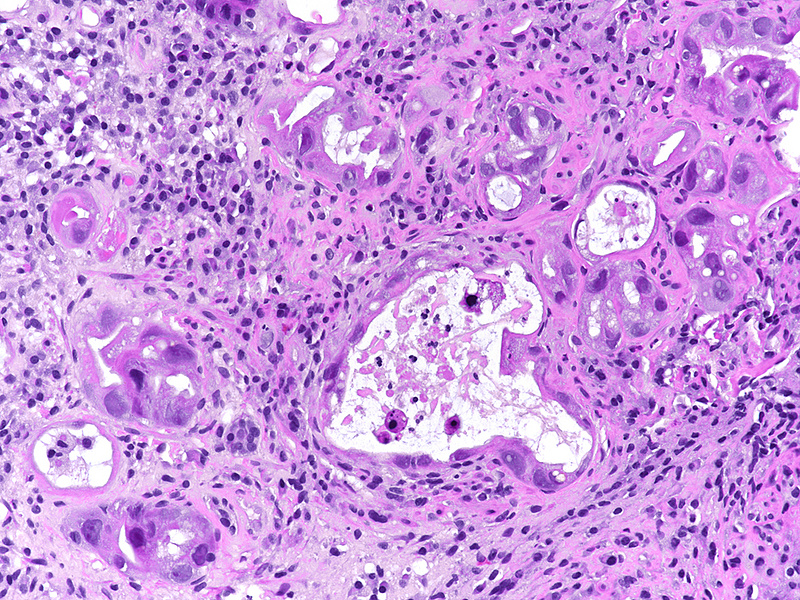

A 41-year-old female with ocular malignant melanoma, metastatic to both lobes of the liver, presented with nausea, vomiting and epigastric pain. Upon endoscopy, a large ulcerated lesion, extending from the corpus to the duodenal bulb, was detected (Panel A). Upon histology, ballooning cells with mild to moderate nuclear atypia were observed within the surface and foveolar epithelium (Panel B-C). Marked nuclear pleomorphism, hyperchromasia and loss of polarity, along with increased cytoplasmic eosinophilia were present within the deep gastric glands (Panel D). Mitotic figures were not seen, and  the  Ki-67 labelling index was low (Panel E). p53 overexpression was noted in the atypical cells, however with  heterogeneous staining, thereby indicating an activated wild-type pattern (Panel F).

The presented case demonstrates severe atypia of the gastric epithelium, which exceeds what is typically seen in ischaemic injury and may lead to the erroneous diagnosis of dysplasia and/or malignancy. Drug toxicity explains these findings. Specifically, fotemustine causes interstrand crosslinking of DNA, which prevents DNA replication, and ultimately leads to apoptosis in a p53 dependent manner. Interestingly, Ki-67 labeling was low in our case. This may be attributable to the fact that the highest levels of nuclear Ki-67 staining are reached during the M phase of the cell cycle, which the epithelial cells failed to enter due to the drug effect (Varelas et al. 2022).